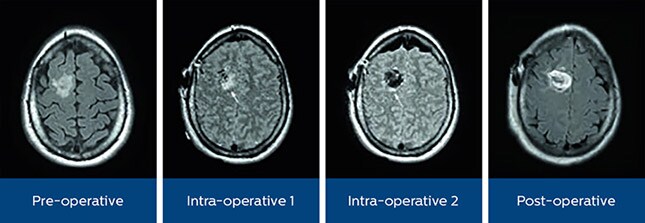

Removing as much of a brain tumor as possible during initial neurosurgery can make a critical difference in the prevention of recurrence and the survival rates. At the same time, surgeons want to reduce the chance of damage to vital areas. Due to brain shift, it can be difficult to determine the tumor margins during surgery. With intra-operative MRI, surgeons have on-the-spot access to MR images to visualize the extent of tumor resection and update the surgical plan if necessary. The Philips MR-OR solution provides fast and smooth patient transfer between the OR and connected MR room for intra-operative imaging. This material is not for distribution/use in the USA

“The clear benefit is that in cases where the MR-OR setup helps to visualize an incomplete resection, we can immediately address the issue using updated navigation data and thus avoid a second surgery. In addition, the final intra-operative MR replaces the post-operative one that we used to perform.”

“For us, it’s a consideration of patient care,” says Lisa Scarpace, Clinical Coordinator iMRI at the Henry Ford Hospital in Detroit, USA. “When after surgery it turns out that a little bit of tumor is left, patients may need extensive radiation or chemotherapy, or sometimes a patient needs to be taken back to surgery a second time within the same week. MR-OR helps us monitor the extent of resection, that is a big advantage.”